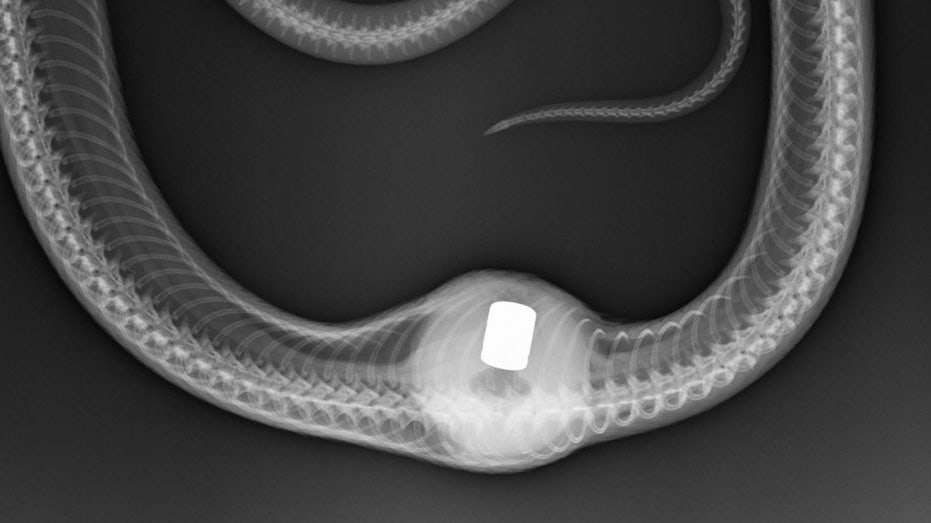

Snake in Maryland is recovering after accidentally swallowing a gear shift knob: Very 'unusual case'

Warning: graphic imagesA rat snake in Maryland is on the road to recovery after she accidentally swallowed a gear shift knob, an animal rehabilitation organization wrote on its Instagram page."This ra...